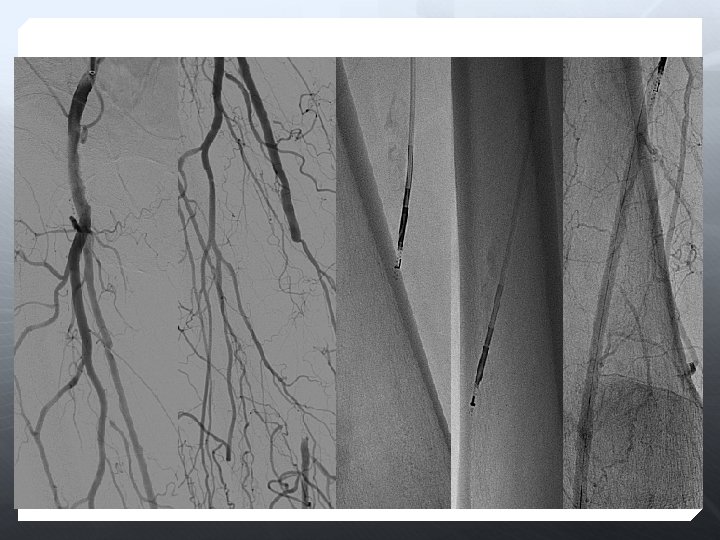

DİZALTI

Amaç uzun dönem açıklık değil, akımı restore etmek Olabildiğince çok damar restrore edilmeli Total ayak perfüzyonu iyileştirilir 3 damar run-off ile daha iyi SFA açıklığı sağlanır Oklüzyona karşı daha dirençli

Anjioplasti Subintimal anjioplasti Cutting-balon DEB Stent (BES, SES) DES Aterektomi Excimer laser